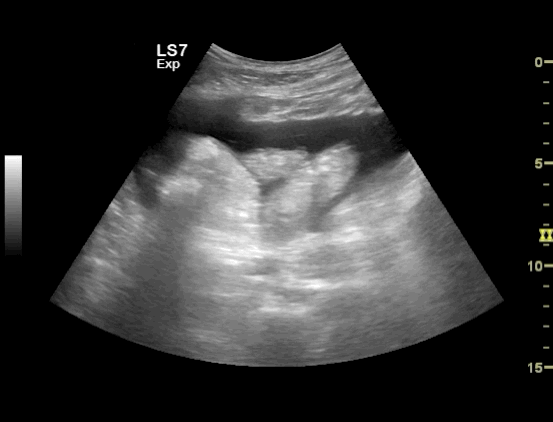

The video clip shows a small rim of free fluid along the liver edge with extensive free fluid noted amongst the intestinal loops

Free Fluid in between the Intestinal loops